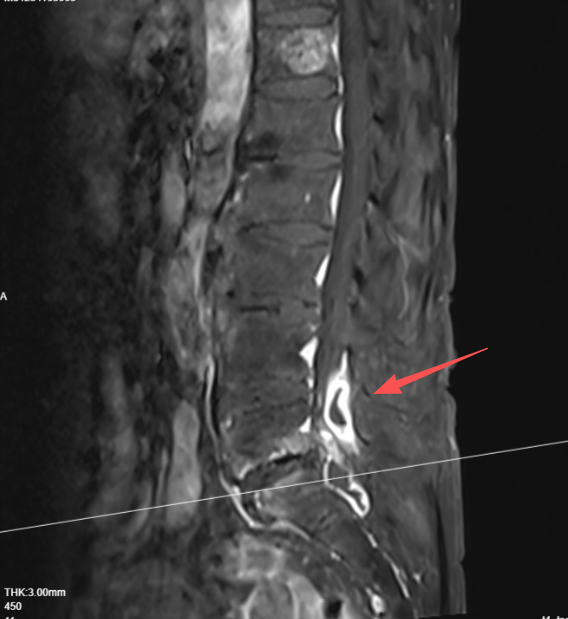

近日,老人来武汉探亲,在家人的陪伴下来到武汉市第四医院常青院区就诊。医生接诊后为其进行了详细检查,磁共振检查提示患者腰椎硬膜外有明显异常信号,高度怀疑感染存在感染灶。随后医生为其进行手术,术中发现患者硬膜外软组织存在感染性病变。据手术医生、常青院区骨二科副主任王威医生介绍,孙婆婆的感染存在时间较长,炎症已经导致部分组织机化,形成瘢痕和硬结,进而刺激和压迫到神经。

”椎间盘突出和感染“夹击”,神经严重受压,症状就会加重“据王威副主任介绍,孙婆婆的椎间盘突出也较为严重,压迫神经。这是其持续腰痛、腿麻的根本原因。通过微创手术,医生为其彻底清除感染灶,同时解除突出的椎间盘对神经的压迫。术后患者疼痛、麻木消失,目前已顺利康复出院。